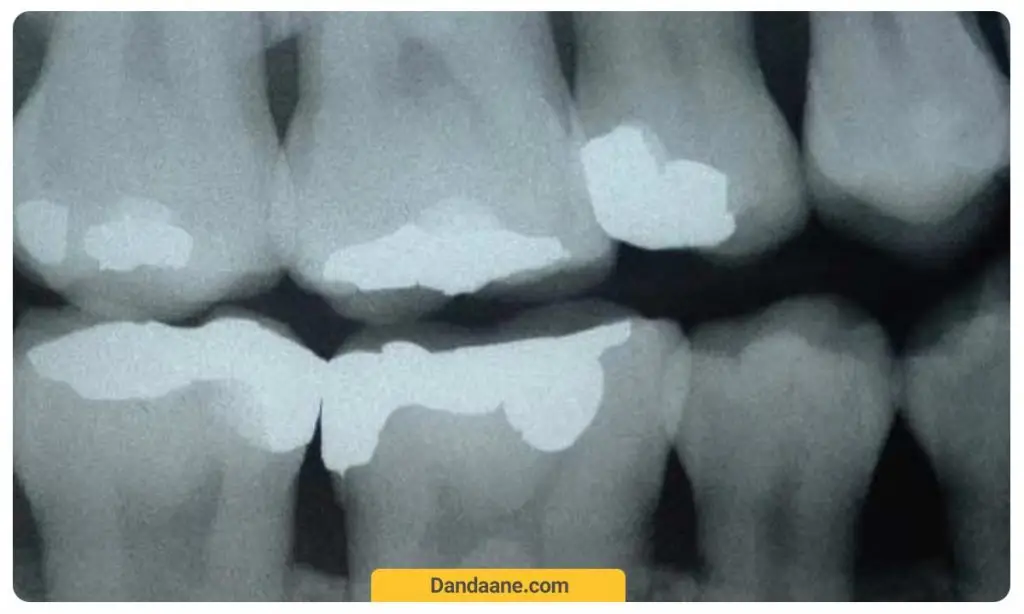

عکس بایت وینگ دندان (Bitewing)

عکسبرداری بایت وینگ تاج یا روکش دندان را به خوبی به دندانپزشک نشان می هد. در این روش دندانپزشک از هر طرف صورت و یا هر دو طرف عکس می گیرد. در هر عکس دندان بایت وینگ دندان های مولر (دندان های عقب) و دندان های پرمولر (آسیاب کوچک) در بالا و پائین و در واقع جزئیات دندان های بالا و پائین یک سمت دندان را نشان می دهد.

همچنین از عکسبرداری بایت وینگ برای تعیین میزان مناسب بودن یا نبودن روکش های دندانی و یا ترمیم های دیگری مانند بریج دندان استفاده می شود. به جز این، می توان وضعیت پر کردکی های دندانی را می توان با بایت وینگ به صورت دقیق ارزیابی کرد.

هزینه عکس بایت وینگ معمولا از قیمت و هزینه عکس دندان opg کمتر و برابر با 70 تا 100 هزارتومان است.